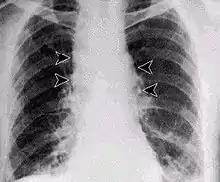

Inhalational anthrax, mediastinal widening